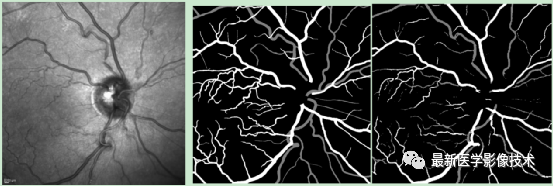

4、验证集分割结果,左图是眼底图像,中间是金标准图像,右图是分割图像